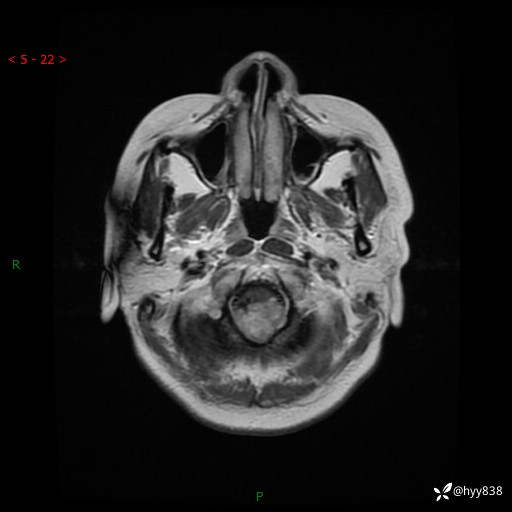

性别:女

年龄:47岁

简要病史:头晕1年余,间断恶心不伴呕吐

颅脑MRI平扫+DWI